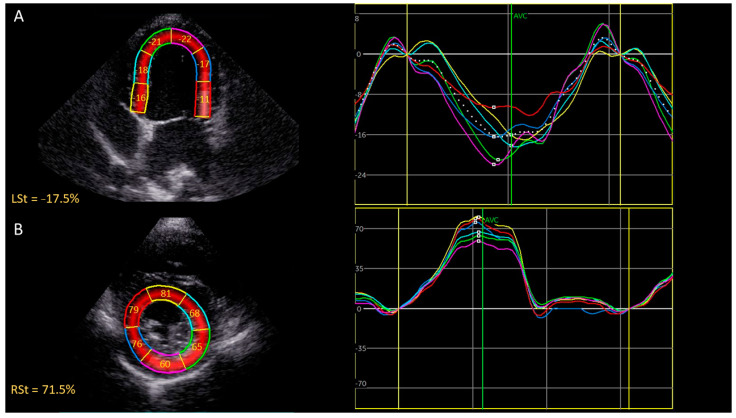

Combretastatin A4-phosphate (CA4P)是一种血管破坏剂,最近被描述用于治疗犬实体肿瘤。传统的超声心动图和脉冲波组织多普勒成像并没有显示狗的心脏毒性,然而,评估接受心脏毒性化疗的人类心肌损伤的金标准是二维斑点跟踪超声心动图。目前的研究评估了单剂量CA4P对狗的心脏毒性作用,使用峰值收缩应变测量和这些测量的可变性。回顾性分析了7只健康小猎犬和5只接受CA4P治疗的犬癌患者的超声心动图检查结果。测定CA4P给药前和给药后24 h的收缩区域纵向应变峰值(LSt)、收缩区域周向应变峰值(CSt)和收缩区域径向应变峰值(RSt)。将峰值收缩应变测量值与血清心肌肌钙蛋白I (cTnI)进行比较。为了量化观察者内部和观察者之间的测量变异性,选择了7个超声心动图检查,每个应变参数由3个观察者连续3天测量。CA4P治疗后,LSt和CSt的中位数分别下降了21.8% (p = 0.0005)和12.3% (p = 0.002),而RSt的中位数差异无统计学意义(p = 0.70)。LSt降低与血清cTnI值升高相关(Spearman ρ = -0.64, p = 0.02)。LSt、CSt和RSt的观察者内变异系数(CV)分别为9%、4%和13%,而相应的观察者间变异系数(CV)分别为11%、12%和20%。我们的研究结果表明,局部峰值收缩应变测量可能有助于血管破坏剂引起的心脏毒性的早期检测,并且LSt可能有希望用于犬癌症患者的随访。

Combretastatin A4-phosphate (CA4P) is a vascular disrupting agent that was recently described for the treatment of solid canine tumors. Conventional echocardiography and pulsed wave tissue Doppler imaging did not reveal cardiotoxicity in dogs, however, the gold standard for assessing myocardial damage in humans receiving cardiotoxic chemotherapeutics is two-dimensional speckle-tracking echocardiography. The current study evaluated the cardiotoxic effect of a single dose of CA4P in dogs using peak systolic strain measurements and the variability of these measurements. Echocardiographic examinations of seven healthy beagles and five canine cancer patients that received CA4P were retrospectively reviewed. Peak systolic regional longitudinal strain (LSt), peak systolic regional circumferential strain (CSt), and peak systolic regional radial strain (RSt) were measured before and 24 h after administration of CA4P. Peak systolic strain measurements were compared to serum cardiac troponin I (cTnI). To quantify intra- and inter-observer measurement variability, seven echocardiographic examinations were selected and each strain parameter was measured by three observers on three consecutive days. After CA4P administration, the median LSt and CSt values decreased by 21.8% (p = 0.0005) and 12.3% (p = 0.002), respectively, whereas the median RSt values were not significantly different (p = 0.70). The decrease in LSt was correlated with increased serum cTnI values (Spearman rho = -0.64, p = 0.02). The intra-observer coefficients of variation (CV) were 9%, 4%, and 13% for LSt, CSt, and RSt, respectively, while the corresponding interobserver CVs were 11%, 12%, and 20%. Our results suggest that regional peak systolic strain measurements may be useful for the early detection of cardiotoxicity that is caused by vascular disrupting agents and that LSt may be promising for the follow-up of canine cancer patients.